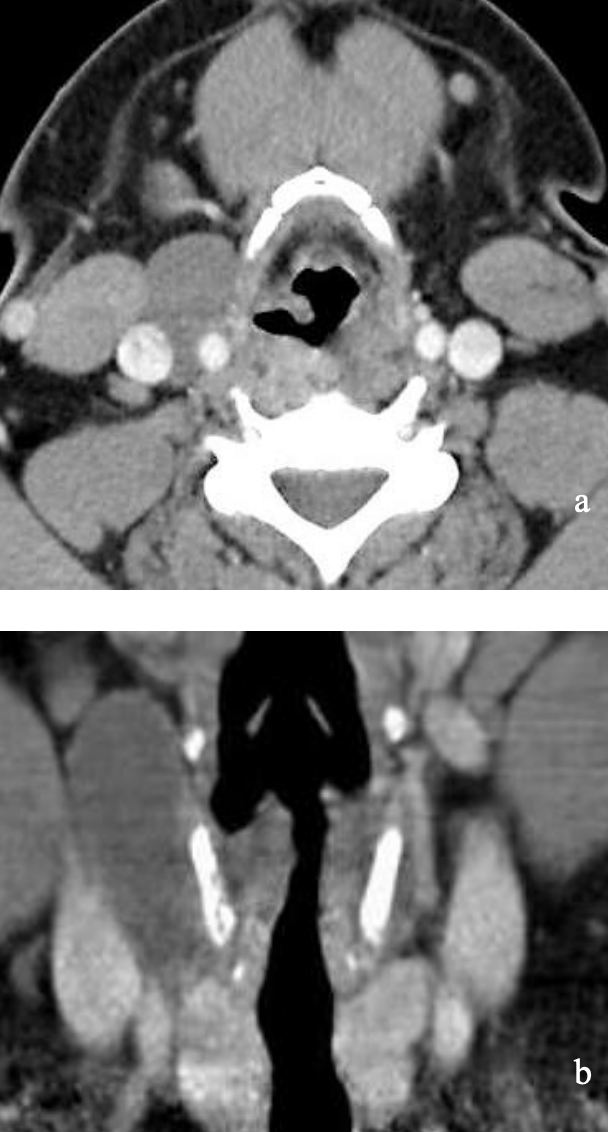

Figure 32: Infected 4th branchial cyst displacing thyroid gland anterolaterally

Figure 33: Infected 4th branchial cyst in paratracheal region extending to pyriform fossa

These are extremely rare. They almost always occur on the (L) side and typically are misdiagnosed as “acute suppurative thyroiditis”, or cervical abscesses that have been repeatedly drained (Figures 32, 33).